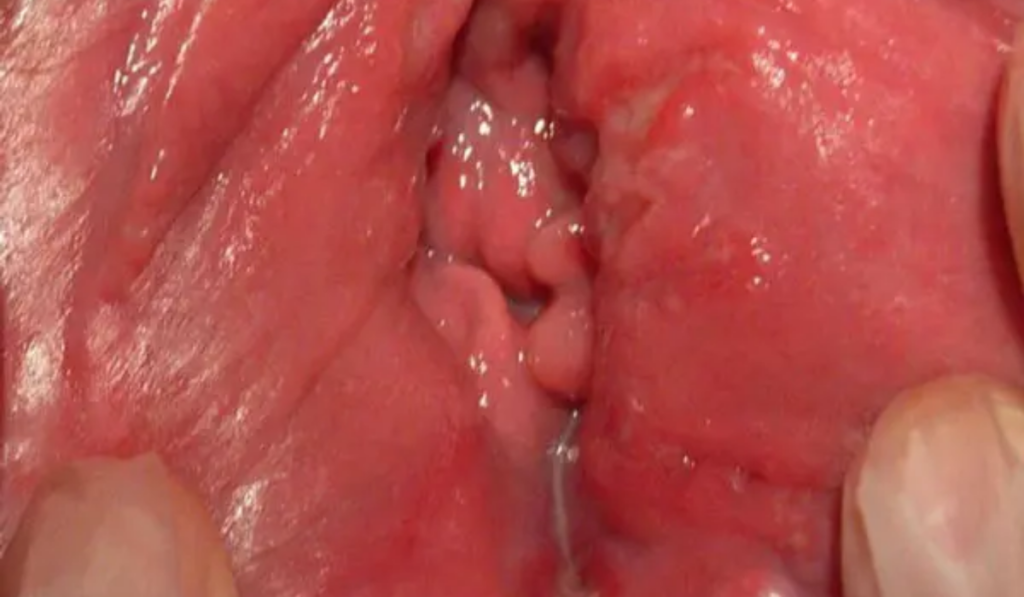

3. Hình ảnh ngứa vùng kín do trùng roi Trichomonas

- Dấu hiệu nhận biết: Ngứa rát, tiểu buốt, tiểu rắt.

- Hình ảnh đặc trưng: Khí hư có màu vàng xanh, loãng và thường có bọt khí. Cổ tử cung có thể xuất hiện các điểm xuất huyết nhỏ như hình “quả dâu tây”.